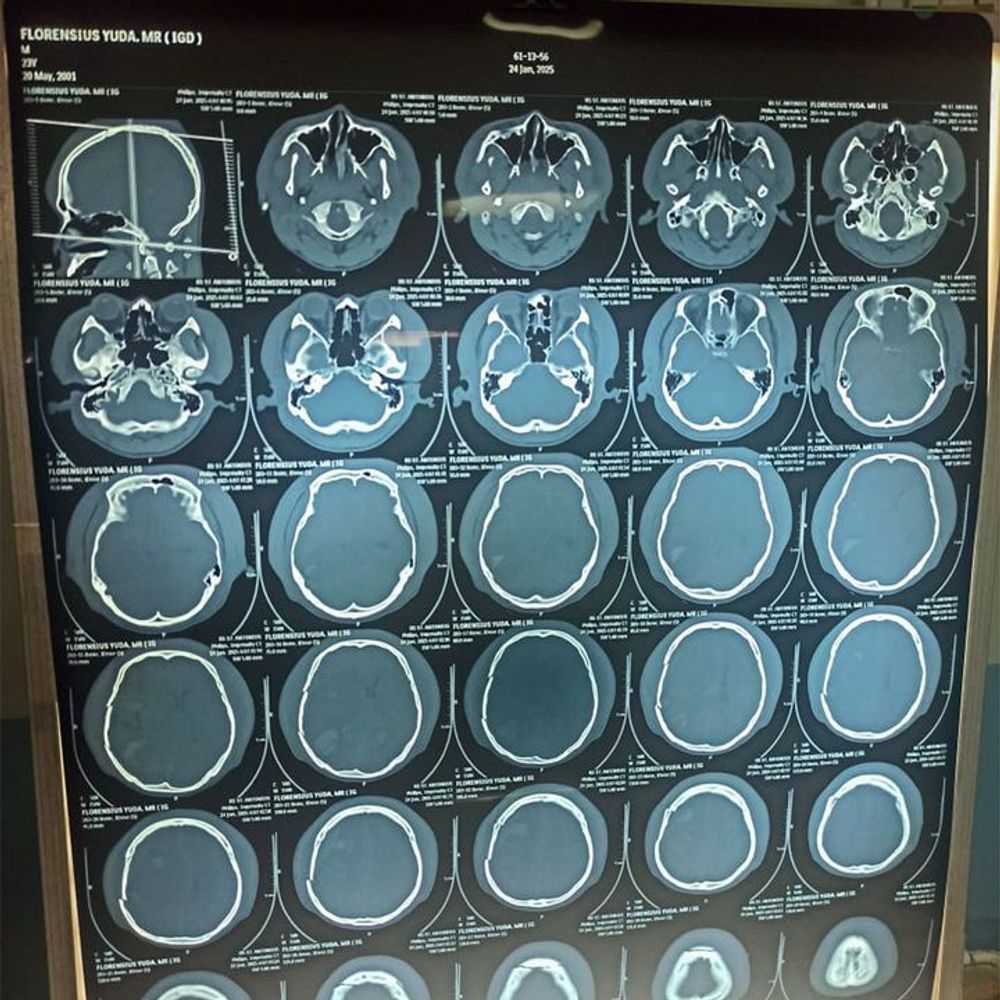

He was found unconscious an hour later and rushed to a local hospital. Due to limited facilities, Yuda had to be transferred to a better-equipped hospital four hours away. Tests showed severe bleeding in his brain, forcing doctors to urgently operate, including removing part of his skull to relieve the swelling. Since then, Yuda has remained in a coma for over two weeks.